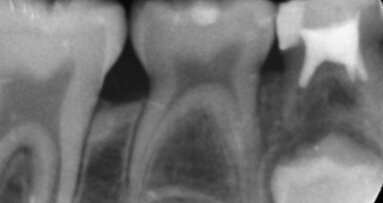

Una ricerca dell'Università della Pennsylvania ha dimostrato che i microrobot possono accedere a superfici del canale radicolare difficili da raggiungere, interrompere i biofilm e recuperare campioni diagnostici, consentendo così un piano di trattamento più individualizzato (Image: CI Photos/Shutterstock).

La causa principale del fallimento del trattamento endodontico è la disinfezione incompleta del canale radicolare, con conseguente infezioni endodontiche e parodontite. Uno dei motivi è la complessa anatomia del canale radicolare, che rende difficile l'efficace rimozione del biofilm, e finora i mezzi per diagnosticare e valutare l'efficacia della disinfezione sono stati limitati.

«I principali limiti delle attuali strategie endodontiche sono triplici: la mancanza di precisione nel targeting dei biofilm che infettano la regione apicale e la complessità anatomica del canale radicolare, nonché la difficoltà di reperire campioni di biofilm per la diagnosi. Per quanto ne sappiamo, non esiste un approccio in grado di effettuare contemporaneamente il prelievo di campioni e il trattamento antimicrobico in endodonzia», ha commentato l'autore principale il Dr. Alaa Babeer della Penn Dental Medicine, sulla pertinenza dei risultati dello studio nei trattamenti endodontici. «I nostri risultati dimostrano la fattibilità di utilizzare la versatilità dei microrobot per accedere a superfici endodontiche difficili da raggiungere per eseguire l’uccisione, la rimozione e il recupero di biofilm per il rilevamento microbico in tempo reale. Inoltre, dimostriamo la fattibilità del tracciamento robotico all’interno del canale utilizzando le attuali modalità di imaging clinico», ha proseguito.